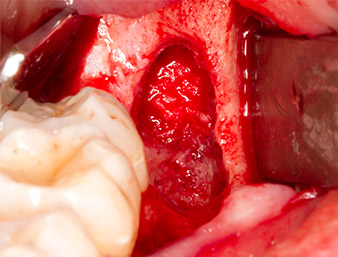

The tissue above the root remnant was not completely ossified and consisted for the most part of granulation tissue modified by inflammation (Fig. 4).